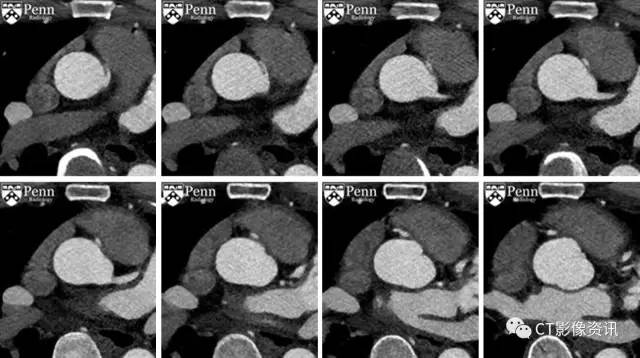

门控冠脉CTA成像,轴位图像

复习轴位图像

影像学描述 右冠状动脉从左侧冠窦异常起源,右冠与冠窦之间夹角狭窄,开口呈狭缝状改变,在主动脉根部和近端肺动脉干之间走形(或者可能恰好邻近肺动脉瓣,示例图片可能显示的不好)。右冠状动脉近端主干的管径减小。未见冠状动脉钙化。